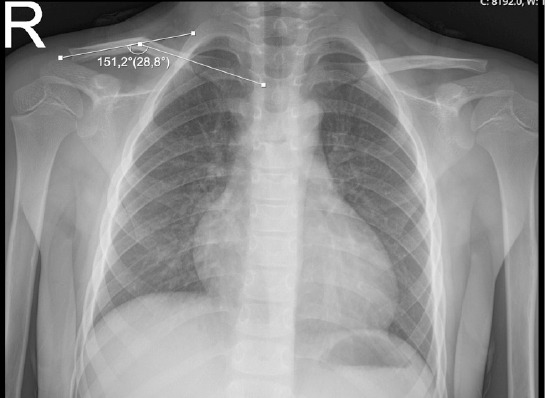

Methods: Patients were divided into two groups based on the preferred conservative management method: Group 1 (arm sling) and Group 2 (figure-of-eight bandage). The degree of angulation and shortening was measured at initial admission and during follow-up. Demographic characteristics and radiological data were compared between the two groups.

Results: Group 1 included 10 girls and 10 boys, while Group 2 included 12 girls and 17 boys (p=0.761). The mean shortening at initial presentation was 7.28+-6.06 mm in Group 1 and 6.65+-5.58 mm in Group 2 (p=0.625). At follow-up, the mean shortening was 6.24+-5.59 mm in Group 1 and 5.59+-4.91 mm in Group 2 (p=0.569). The mean angulation at initial presentation was 21.28+-10.05° in Group 1 and 20.41+-12.23° in Group 2 (p=0.752). At follow-up, the mean angulation was 14.45+-9.41° in Group 1 and 11.82+-10.27° in Group 2 (p=0.189). In intra-group comparisons, no significant difference was found between the initial shortening and follow-up shortening in either group (Group 1: p=0.062; Group 2: p=0.190). A significant reduction in angulation was observed in both groups during follow-up (p=0.001 for Group 1; p=0.001 for Group 2).